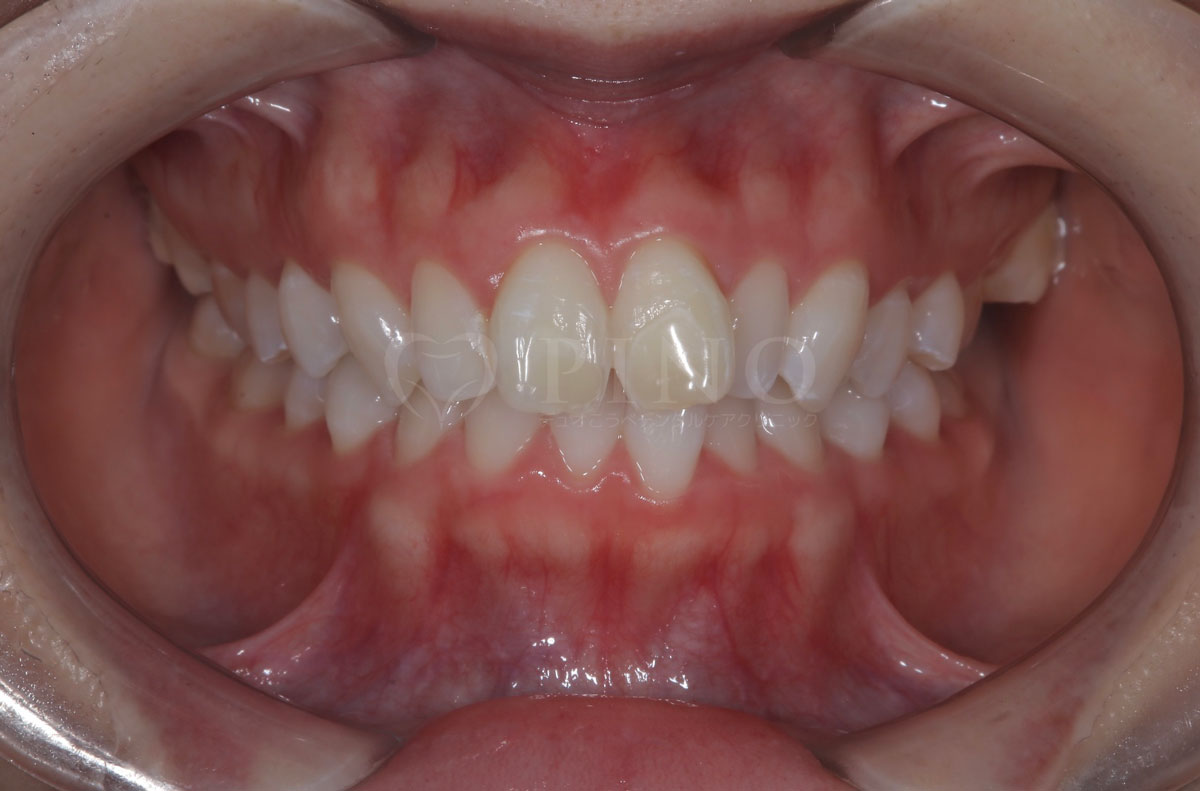

症例4:噛み合わせが深く、下の歯が見えないのが気になる(10代女性)

主訴 噛み合わせが深い、下の歯が見えない 診断名 過蓋咬合(かがいこうごう) 治療方法 マウスピース全顎矯正 抜歯 なし オルソパルス なし 治療期間 1年1ヶ月 費用 746,000円 副作用・注意点 矯正後の後戻りを防ぐためリテーナーの使用が必要となる -